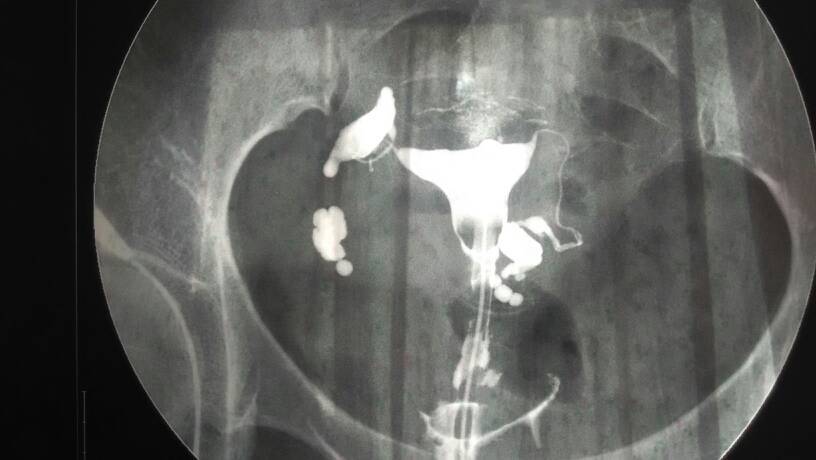

那位医生能帮我看看我的造影片子啊,我结婚三年了都没有怀孕,去年做的一系列检查还做了体温监测,都没什么问题,最后做的造影,大夫看了我的造影片子说我怀孕的几率太小了,只能做试管,可是我不想做试管费用太高了,所以想请专家帮我看看。我有得过结核病,挺严重的,不知道有没有用i我i影响。